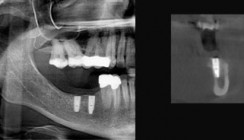

Der Einsatz digitaler Volumentomografie eröffnet ohne Frage ein breites Spektrum an diagnostischen Möglichkeiten (Abb. 1 und 2). Um hierbei jedoch betriebswirtschaftlich sinnvoll agieren zu können, müssen einige wichtige Aspekte berücksichtigt und im täglichen Umgang mit DVTs entsprechend umgesetzt werden. So stellen neben dem großen Investitionsvolumen insbesondere der Datenschutz sowie die Langzeitarchivierung den Praktiker vor große Probleme.